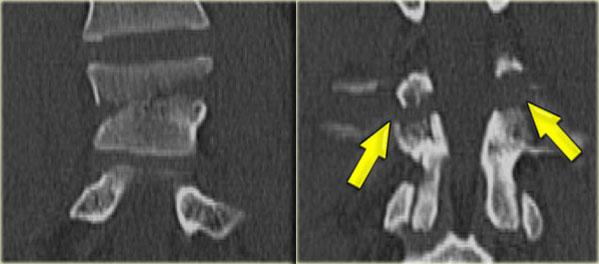

Jumper’s fracture

Bên trái là hình ảnh gãy xương gót và gãy cột sống thắt lưng.

Đây được gọi là ‘gãy xương của người nhảy’ hoặc ‘gãy xương của người tình’, vì thường gặp ở những người nhảy qua cửa sổ để trốn thoát khỏi cảnh sát hoặc người chồng/vợ ghen tuông.

Trong trường hợp này, rõ ràng chúng ta đang nhìn vào một gãy xương không vững, vì đây là gãy xương vỡ tung.

Cả cột trước và cột giữa đều bị tổn thương.

Ngoài ra, có phù nề ở các mô mềm phía sau cho thấy cột sau cũng bị ảnh hưởng.

Cũng cần lưu ý phù nề tủy xương ở các thân đốt sống lân cận do chịu tải trọng dọc trục nghiêm trọng.